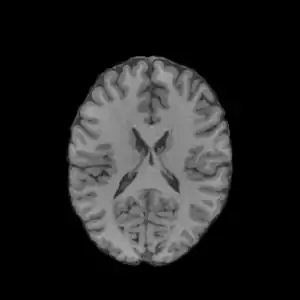

هیستوگرام تصویر

در یک تصویر دیجیتال، مقادیر پیکسلها بیانگر ویژگیهای آن تصویر (مانند میزان روشنایی تصویر و وضوح تصویر) است. هیستوگرام یک تصویر در حقیقت بیان گرافیکی میزان روشنایی تصویر میباشد. مقادیر روشنایی (برای مثال ۰-۲۵۵) در طول محور X بیان شده و میزان فراوانی هر مقدار در محور Y بیان میگردد.

تصویر ۸ بیتی (۰-۲۵۵) در بالا و هیستوگرام همان تصویر در پایین. محور افقی بین ۰ تا ۲۵۵ و محور قائم نشانگر تعداد پیکسلها است.